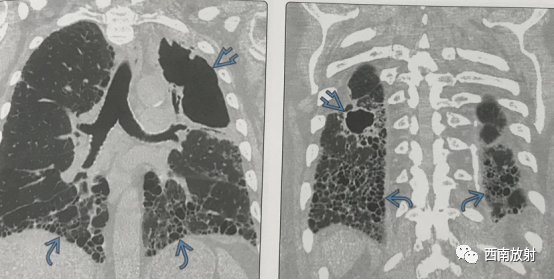

▲图:冠状位平扫CT显示下叶蜂窝影(来自肺纤维化),以及左肺上叶大的空洞。纤维空洞型非结核分枝杆菌感染通常见于肺气肿,以及右肺下叶小空洞。小空洞在胸上可很难辨认,可能由是同时存在的肺疾病。(病例来自《肺部高分辨率CT》译者:赵绍宏 聂永康)